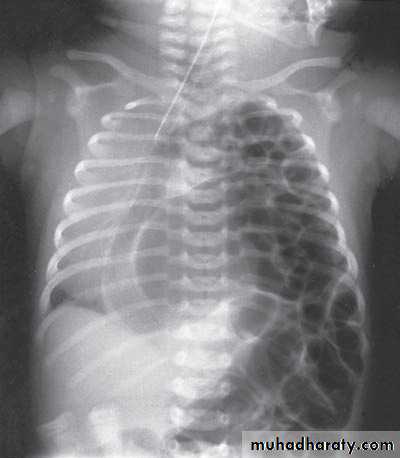

1-chest x-ray.2-Alternatively, a barium study will show bowel within the thoracic cavity when there is a diaphragmatic hernia.

During intra-uterine development, the small bowel, stomach, spleen and left lobe of the liver pass through the defect in the diaphragm into the chest, limiting the space available for the developing lung. This causes lung hypoplasia.

1-cyanosed with severe respiratory distress

within minutes of birth(pulmonary hypoplasia is severe).

2-tachypnoea, increased respiratory effort.

3-hyperinfl ated chest and scaphoid abdomen.

4-heart sounds are on the right side.